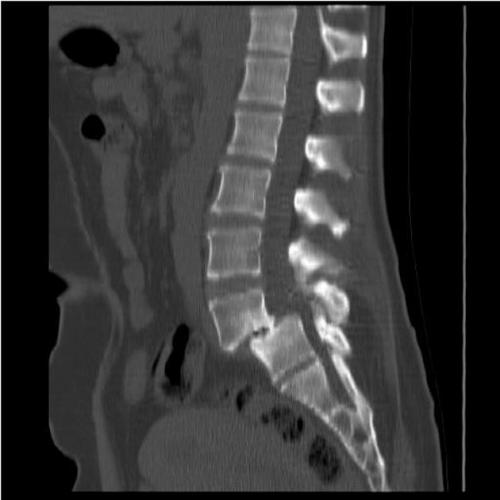

Подтвердить или опровергнуть диагноз позволяет рентген. Он определяет стадию развития заболевания и причину его возникновения. Более информативными методиками считается МРТ или КТ, но их назначают в отдельных случаях для получения развернутой картины состояния пациента.

Диагностировать клиновидное смещение можно с помощью рентгенографии поврежденного отдела в боковой и прямой задней проекции. На ранних стадиях лучше всего изменения зафиксировать при помощи томографии. Это дает возможность диагностировать трещину позвонка, грыжу, изменения в губчатом теле позвонка, остеопорозные изменения.